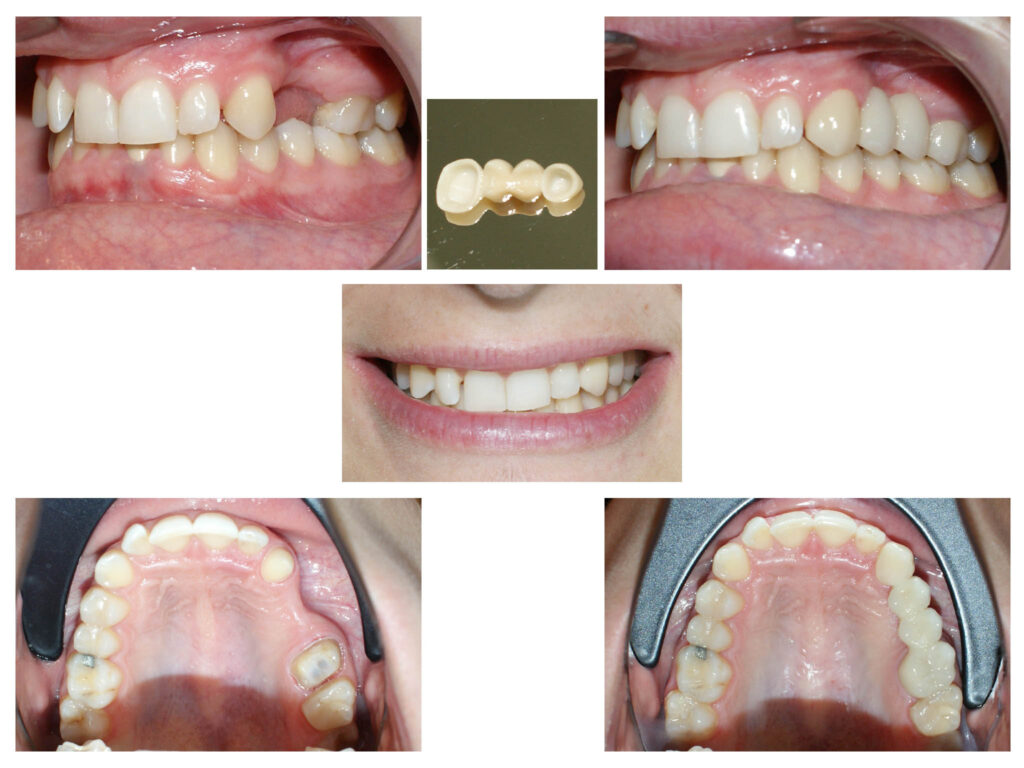

Caz de fațetare a dinților – o modalitate elegantă, estetică și mai ales minim invazivă de schimbare a formei și a dimensiunii dinților.

Zirconiu stratificat

Lucrare protetică din Zirconiu stratificat- integrare estetică- praguri minim invazive pe dinți tineri, vitali – gingii sănătoase